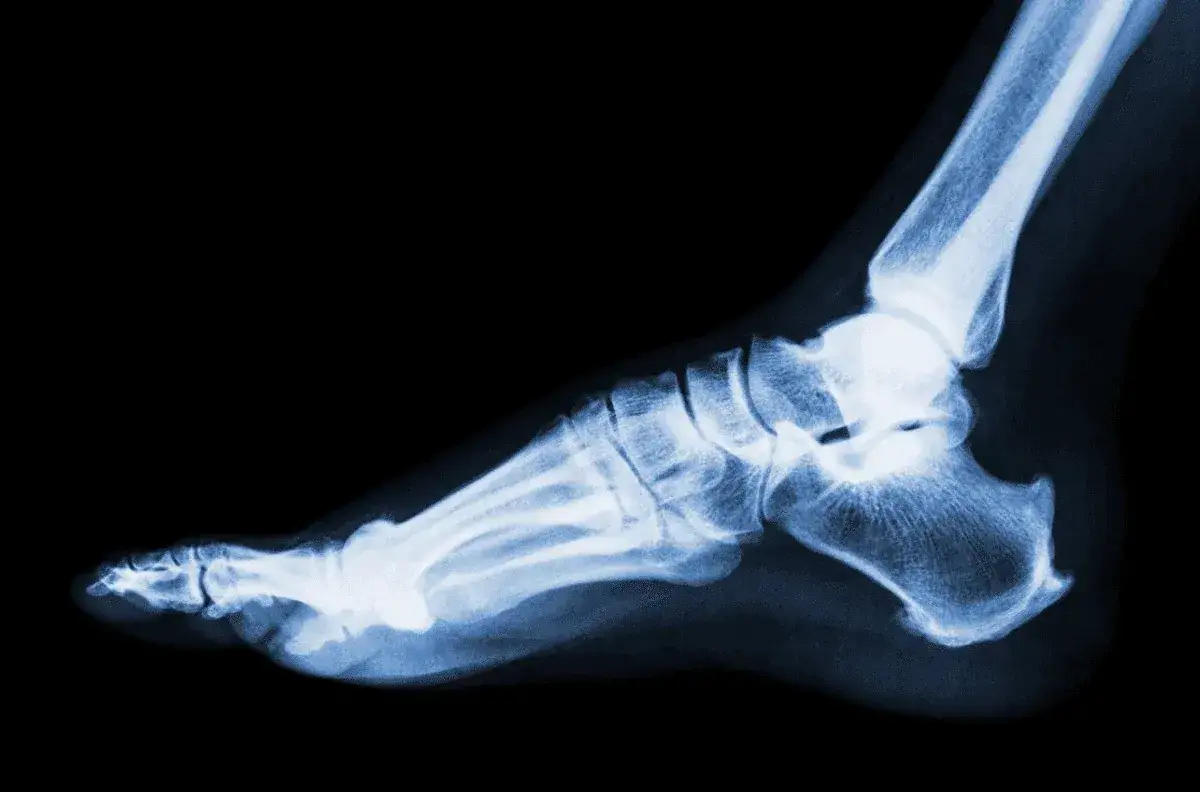

Jakie badania mogą być potrzebne przy urazie kostki?

W przypadku podejrzenia skręcenia kostki, lekarz może zalecić wykonanie kilku badań diagnostycznych. Najczęściej stosowane to rentgen, który pomoże wykluczyć złamania, oraz rezonans magnetyczny (MRI), który dostarcza szczegółowych informacji o uszkodzeniach tkanek miękkich, takich jak więzadła. W niektórych przypadkach może być również konieczne wykonanie ultrasonografii, aby ocenić stan stawu.

Badania te są kluczowe dla postawienia właściwej diagnozy i zaplanowania odpowiedniego leczenia. Wczesne wykrycie poważnych uszkodzeń może znacznie przyspieszyć proces rehabilitacji i pomóc w uniknięciu długotrwałych problemów zdrowotnych.

Oprócz objawów, badania diagnostyczne, takie jak rentgen czy rezonans magnetyczny, są niezbędne do oceny stanu kostki i wykluczenia poważniejszych uszkodzeń. Właściwe postawienie diagnozy i wdrożenie odpowiedniej rehabilitacji po skręceniu kostki, zwłaszcza w przypadku poważnych urazów, jest kluczowe dla przywrócenia pełnej funkcjonalności stawu. Ignorowanie objawów lub opóźnianie wizyty u lekarza może prowadzić do poważnych konsekwencji zdrowotnych, dlatego warto być czujnym na wszelkie niepokojące sygnały.